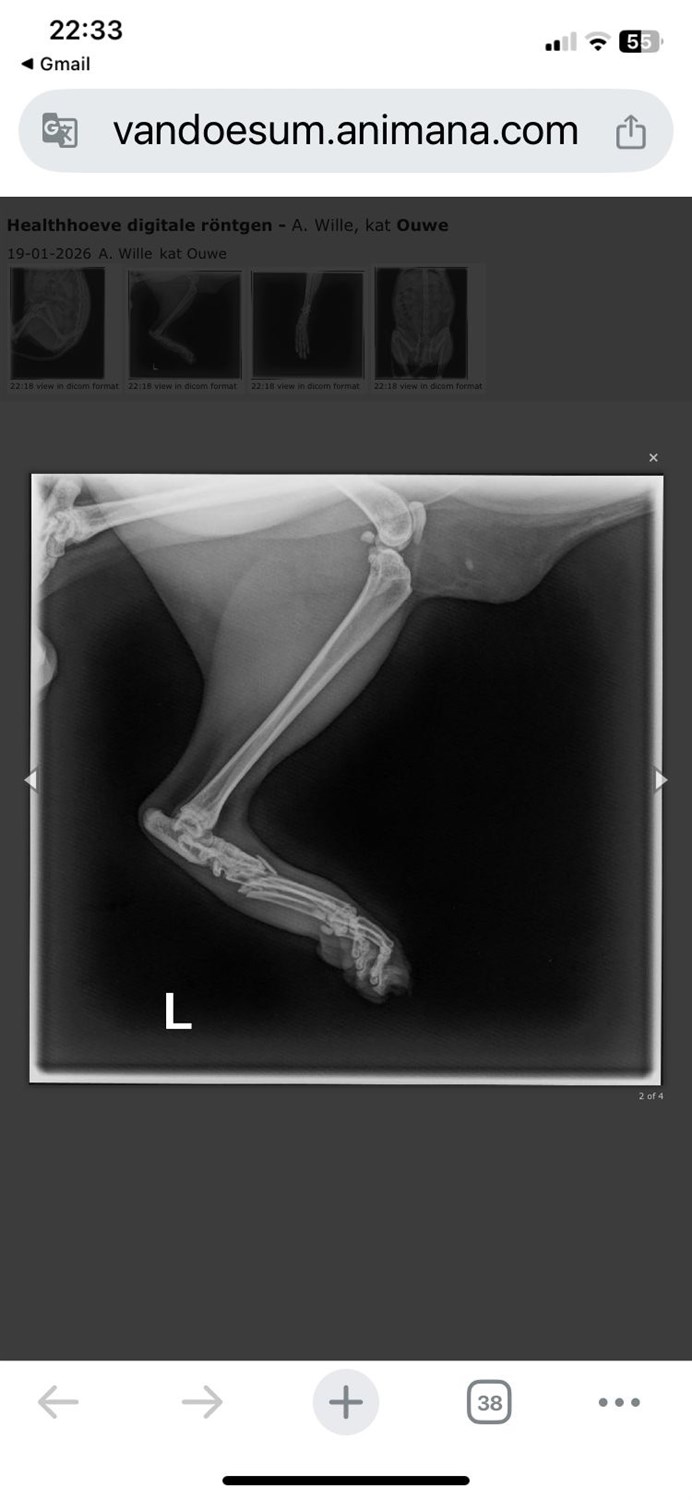

Na een narcose en foto's bleek dat je was aangereden en dat je achterpoot helemaal doormidden gebroken was 😞, ook aan je nagels was te zien dat je hebt gevochten voor je leven om terug naar je huisje te komen buiten, wat niet helemaal lukte.

Aangezien je nog erg vitaal bent, en de breuk gespalkt kon worden gaven zowel de dierenarts als ik dit een kans maar zaten hier begrijpelijk wel kosten aan verbonden.

En kun je voor nu proberen te herstellen met een spalk, al is dit niet voldoende en moet je geopereerd worden.. helaas en begrijpelijk kost dit wel wat geld..